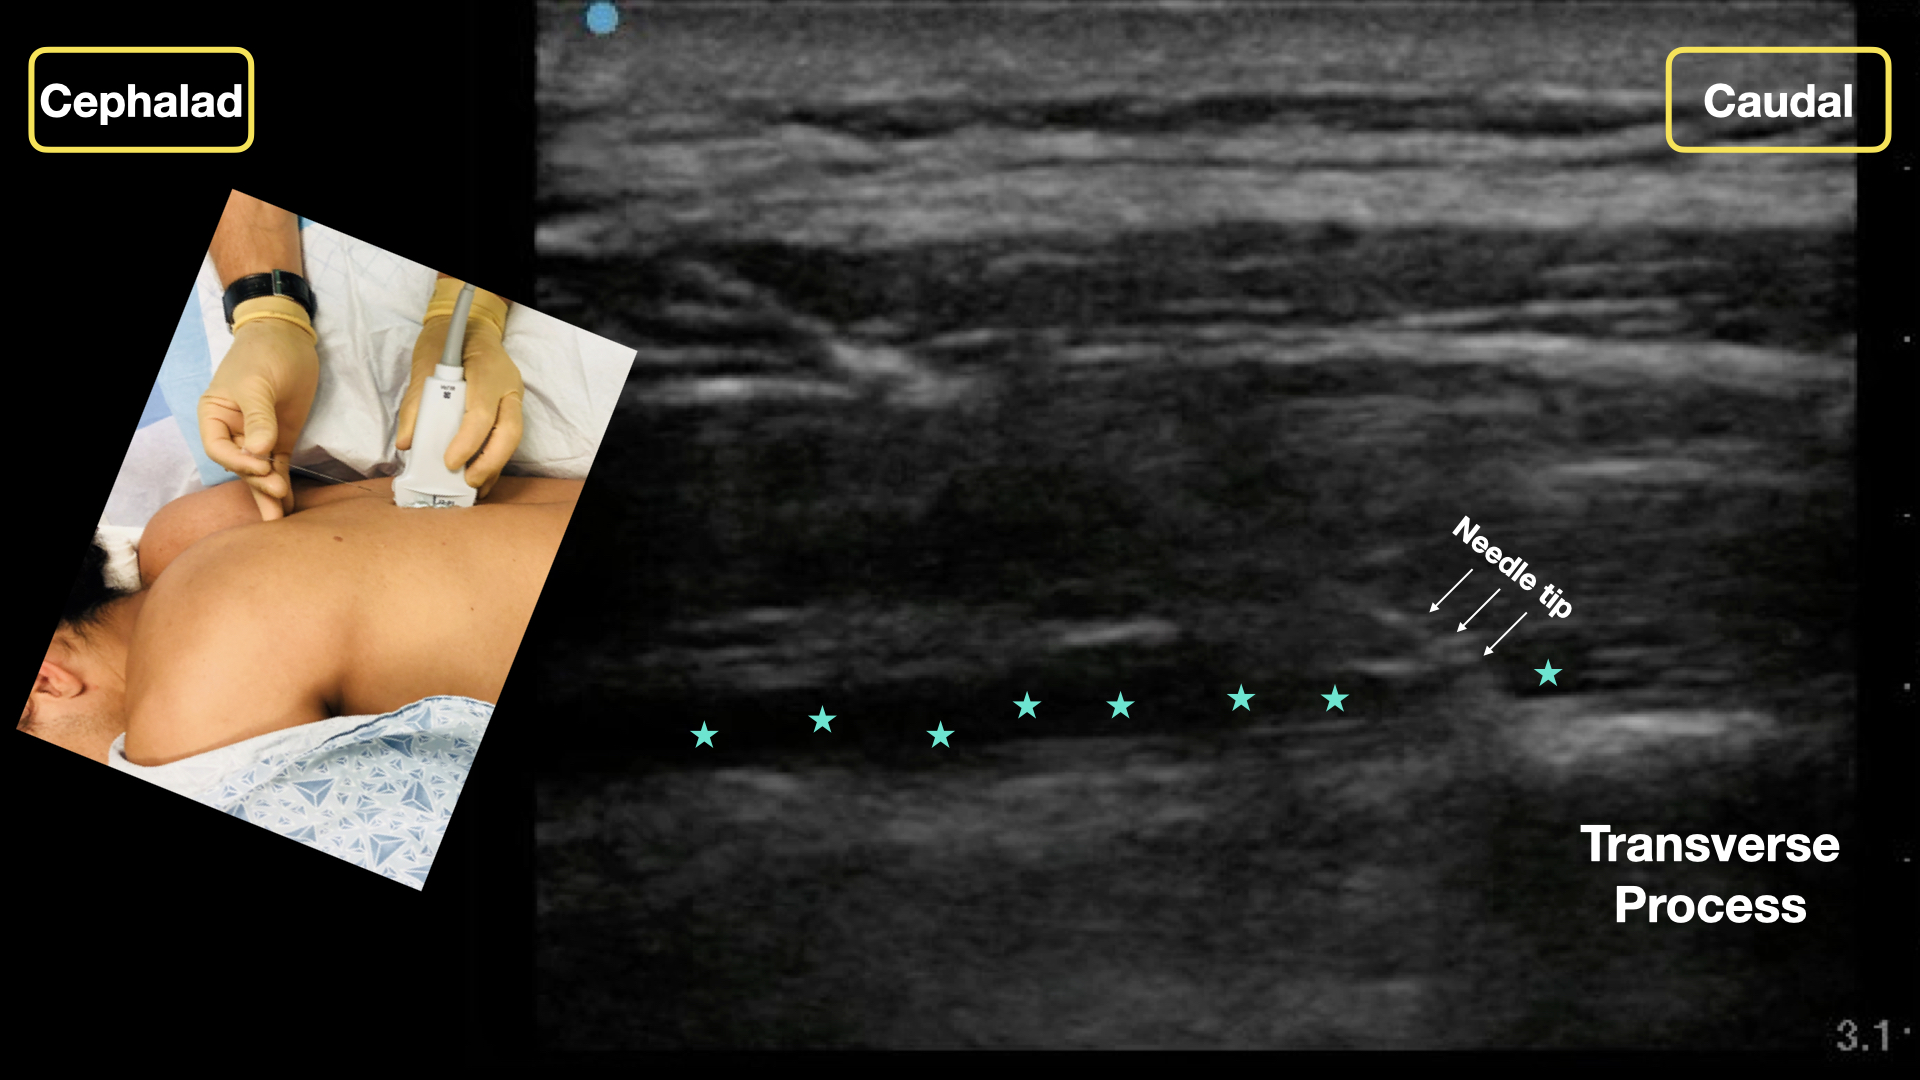

Erector spinae plane block step6

An in-plane cephalad to caudal approach with clear needle tip is recommended. Note the needle tip and anechoic anesthetic tracks in the fascial plane (green stars).

Credit: Arun Nagdev